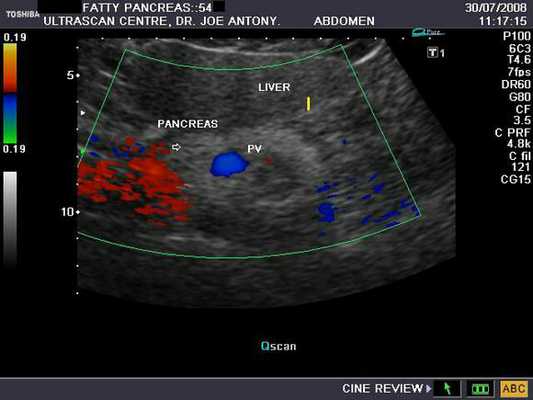

Сонографический внешний вид поджелудочной железы

Поджелудочная железа обычно имеет однородную эхоструктуру при ультразвуковом исследовании, которая является более эхогенной, чем печень, у 52 процентов молодых пациентов и в равной степени эхогенной у 48 процентов. С возрастом железа становится более эхогенной и может стать неоднородной по своей эхоструктуре.

Оценка повышения эхогенности поджелудочной железы

- Степень эхогенности поджелудочной железы 1 степени равна печени.

- Степень эхогенности поджелудочной железы 2 степени несколько выше, чем у печени.

- Эхогенность поджелудочной железы 3 степени явно выше, чем у печени.

- Степень эхогенности поджелудочной железы 4 степени равна забрюшинному жиру.

В здоровье эхогенность связана с возрастом и жировыми отложениями. Однако различия в эхогенности поджелудочной железы в пределах нормальной популяции таковы, что ее оценка имеет ограниченную ценность. При ультразвуковом исследовании эхогенность поджелудочной железы 3 и 4 степени может быть нормальной у взрослых и пожилых людей, но это явление обычно патологическое у детей и подростков. У 10% детей младшего возраста поджелудочная железа может казаться менее эхогенной, чем печень, тогда как у недоношенных новорожденных и младенцев поджелудочная железа может быть довольно эхогенной. В этих случаях эхогенность поджелудочной железы уменьшается по мере созревания железы.